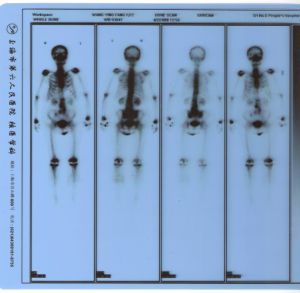

全身顯像

指顯像劑進入人體後,進行全身採集放射性的分布信息,獲取全身性分布圖像。如:全身骨顯像,全身血池顯像,全身淋巴顯像,全身軟組織顯像,全身腫瘤標識物顯像及動物實驗中藥物全身分布顯像等等。進行“全身普查”,對尋找惡性腫瘤的轉移灶十分有價值,全身骨顯像對鼻咽癌、肺癌、乳癌、腸癌、前裂腺癌等最易骨轉移的病例,能早期查出轉移灶。在幫助外科治療(如截肢術)方案決策中亦起到不可忽視的作用。

3、全身骨顯像: 注射顯像劑後的2小時內儘量多飲水500ml以上。檢查前排空小便。如有尿液汚染衣褲、皮膚,應擦洗皮膚及更換衣褲後方可檢查。有植入金屬假肢、假乳房的應告知醫生所植入的部位。檢查前二天不宜作鋇餐、鋇灌腸等檢查。以免鋇劑滯留於腸道影響影像觀察。